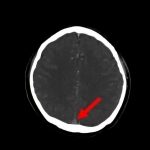

断層撮影